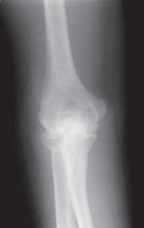

Question 29:

In the setting of acute back pain following trauma with localized spinous process tenderness, a vertebral fracture is a primary concern. Plain radiographs (AP and lateral views) are the initial imaging modality of choice to screen for fractures and assess vertebral alignment. If radiographs are inconclusive or if a complex fracture is suspected, a CT scan would be the next step for better bony detail. MRI is excellent for soft tissue (disc, spinal cord) but may not be the first choice for acute bony trauma, especially if CT is readily available and the primary concern is bone integrity. Bone scan detects metabolic activity, not ideal for acute fracture visualization. Ultrasound has no role in assessing vertebral fractures.